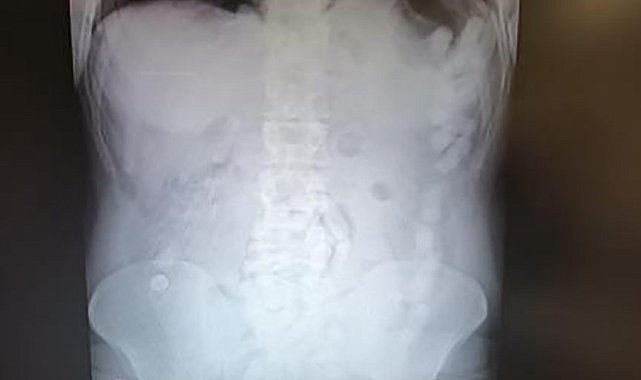

Kayseri'de polis ekipleri tarafından gözaltına alınan şahsın midesinden çıkan 100 kapsülde toplam 729 gram uyuşturucu madde olduğu belirlendi.

Edinilen bilgiye göre, Kayseri İl Emniyet Müdürlüğü Narkotik Suçlarla Mücadele Şube Müdürlüğü ekipleri yabancı uyruklu bir şüphelinin ülkeye giriş yaparak Kayseri'ye geleceğini tespit etti. Şahsı takibe alan ekipler, yerini tespit ettikten sonra operasyon düzenledi. Kayseri Şehir Hastanesinde ultrason çekimi ile yapılan kontrolde şahsın midesinde çok suyada kapsül olduğu tebpit edildi. YApılan operasyonla şahsın midesinden çıkarılan 100 adet kapsülün içerisinde 729 gram uyuşturucu madde ele geçirildi. İşlemlerinin ardından adliyeye sevk edilen şüpheli, çıkarıldığı mahkemece tutuklanarak cezaevine gönderildi.